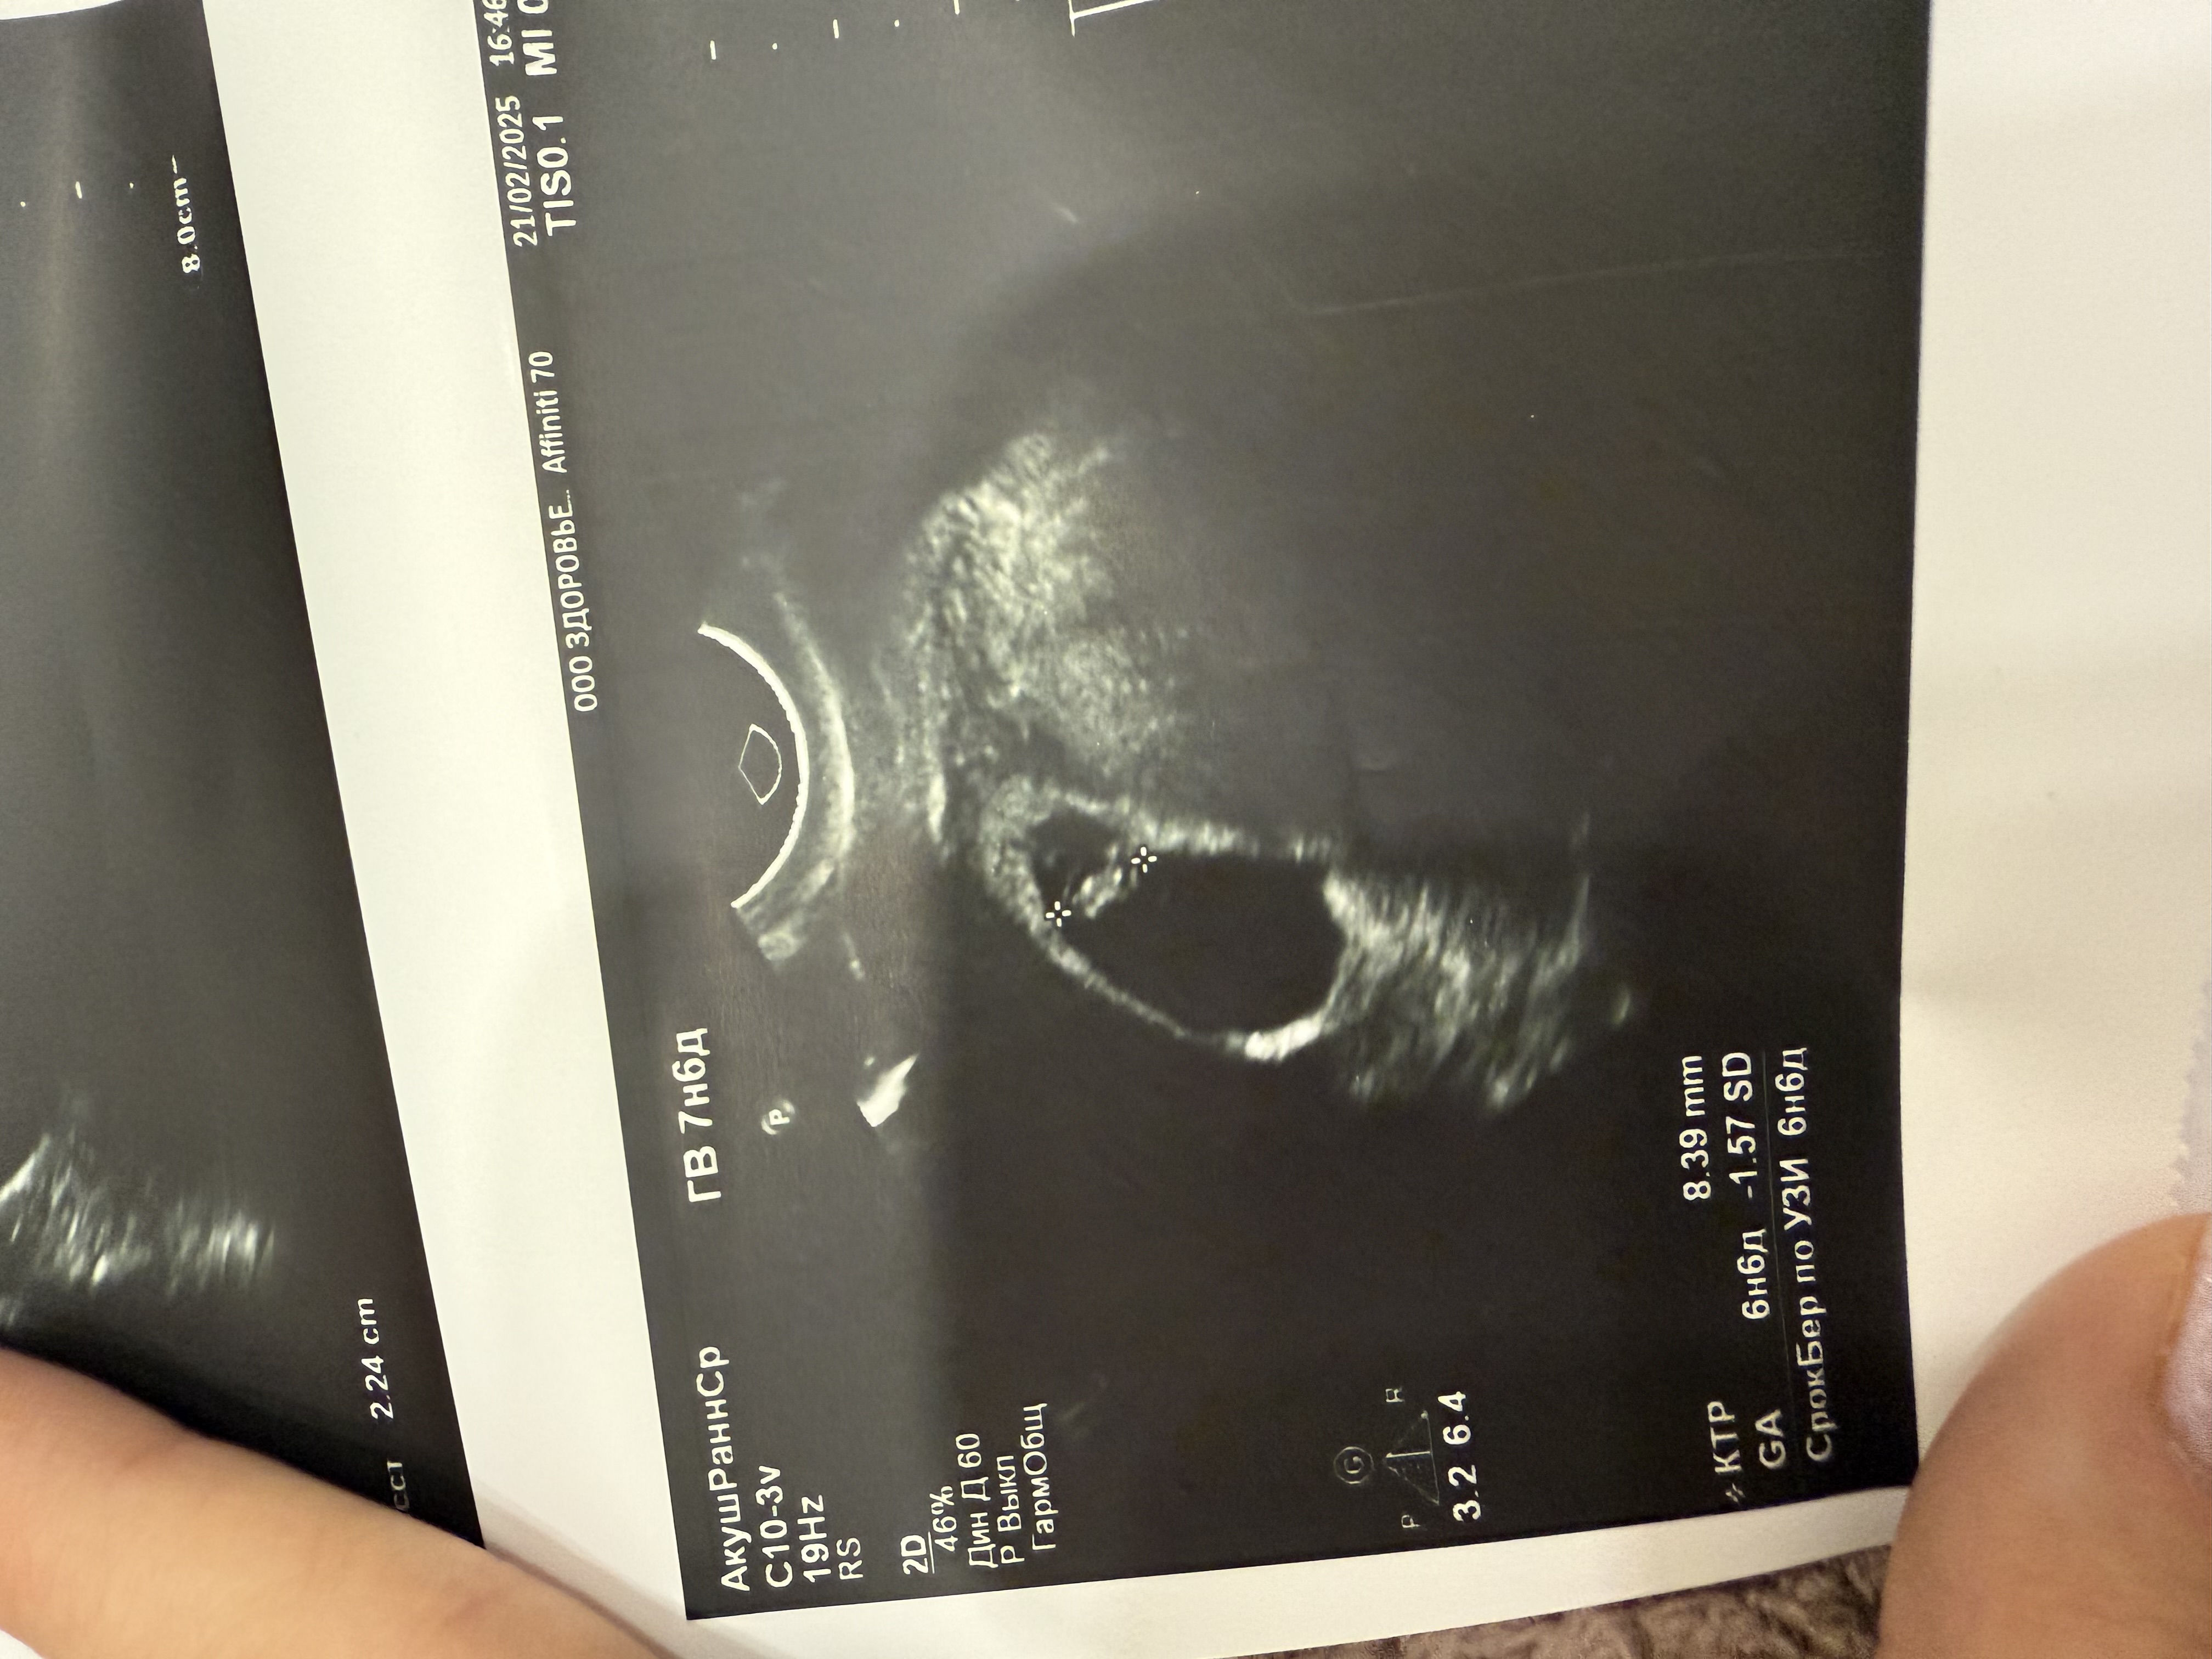

Вот эмбрион 8,4 мм Изображение